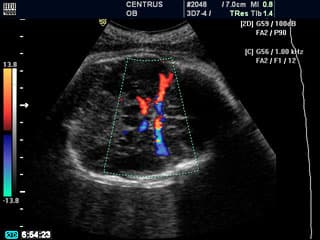

Evalúa el flujo sanguíneo en los vasos fetales y placentarios, permitiendo detectar alteraciones en la circulación que puedan afectar el bienestar del feto.